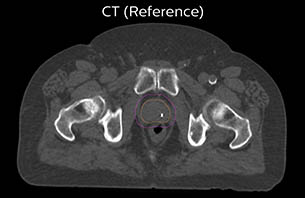

A 77-year-old male with prostate cancer cT3aN0M0, Gleason 8 and PSA 52 μg/L referred to androgen deprivation and radiation therapy with a prescribed dose of 50 Gy to the pelvic lymph node regions and 76 Gy to the prostate.

MR-only simulation workflow The 3D T1W FFE mDIXON sequence provides in-phase, water and fat images in one acquisition. Target and organs-at-risk are delineated on the 3D T2W TSE images. Prostate GTV is shown in orange, PTV in purple. The 3D bFFE sequence is used by the planner to mark the position of the fiducial markers (gold anchors) and contours are transferred to the digitally reconstructed radiographs (DRRs).

Based on the 3D T1W mDIXON images, MR-based density maps (MRCAT) are automatically generated. The VMAT (Volumetric Modulated Arc Therapy) plan is generated in TPS, based on MRCAT as primary image set. During the commissioning phase, dosimetric agreement between MRCAT-based and CT-based dose plans was studied and differences in the PTV dose were found to be minimal (<1% for most patients). Average difference in PTV mean values was 0.8% over the study group (n=62).